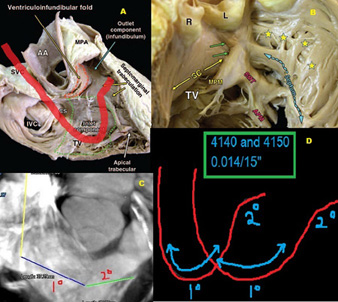

Anatomy for right ventricular lead implantation Herzschrittmachertherapie + Elektrophysiologie

Final position of the wire positioned in the apex of the right

A proposed technique for right ventricular septal pacing